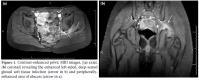

A laboratory examination revealed a white blood cell count of 19.000 cells/mm3, with 74% neutrophils. The hematocrit was 37.5 g/dL, the hemoglobin was 13.4 g/dL, the C-reactive protein (CRP) was 6.87 mg/L, and the erythrocyte sedimentation rate (ESR) was 36 mm/h. The urinalysis, renal function, serum glucose, electrolyte, and creatine phosphokinase levels were normal. The test for HIV was negative, and an abdominal ultrasound was unremarkable. At the beginning, he was diagnosed as having transient synovitis. He was prescribed naproxen, and there was mild clinical improvement. Five days later, contrastenhanced magnetic resonance imaging (MRI) of the pelvis and hips revealed a left-sided, deep-seated gluteal fluid collection consistent with an abscess (Figure 1). The patient was administered intravenous cephazolin and metronidazol. On the ninth day, in addition to the gluteal deep soft tissue abscess, focal osteomyelitis in the posterior of the left acetabulum was detected (Figure 2). Echocardiographic findings were normal, and blood cultures were negative. A combination of vancomycin and amikacin was started instead of the cephazolin and metronidazol. On the 10th day, he underwent an incision, and the left glutean abscess was drained. Staphylococcus aureus (S. aureus) was isolated from the pus culture, and osteomyelitis was confirmed histologically. Because of abdominal pain, a colonoscopy was performed to exclude IBD, but normal colonoscopy findings were observed. The intravenous antibiotics were continued for six weeks, after which time he had completely recovered.